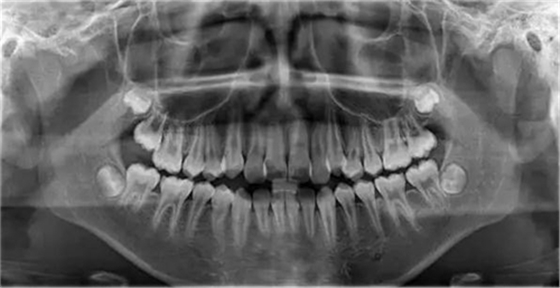

1500865770_445373.jpg1500865976_358577.jpg

此病例主要考慮的是擁擠度,磨牙及尖牙關(guān)系,前牙覆合覆蓋,生長(zhǎng)潛力和智齒。